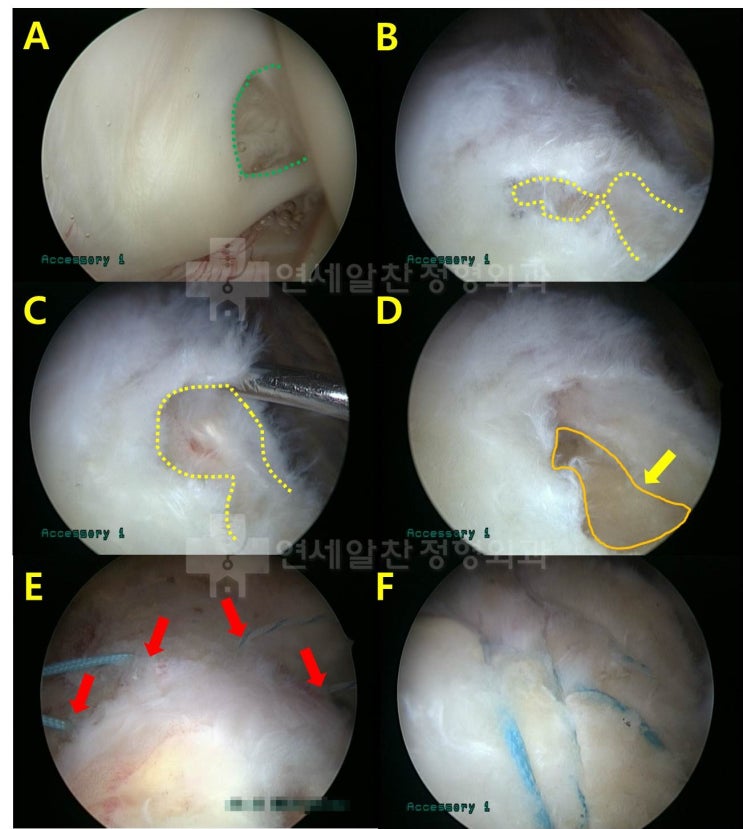

어깨 회전근개 파열 : 보다 단단하게 봉합하는 이열봉합법

안녕하세요. 정형외과 전문의 이동규 입니다. 오늘은 회전근개 파열에서 관절경 수술시 더 단단하게 봉합하...